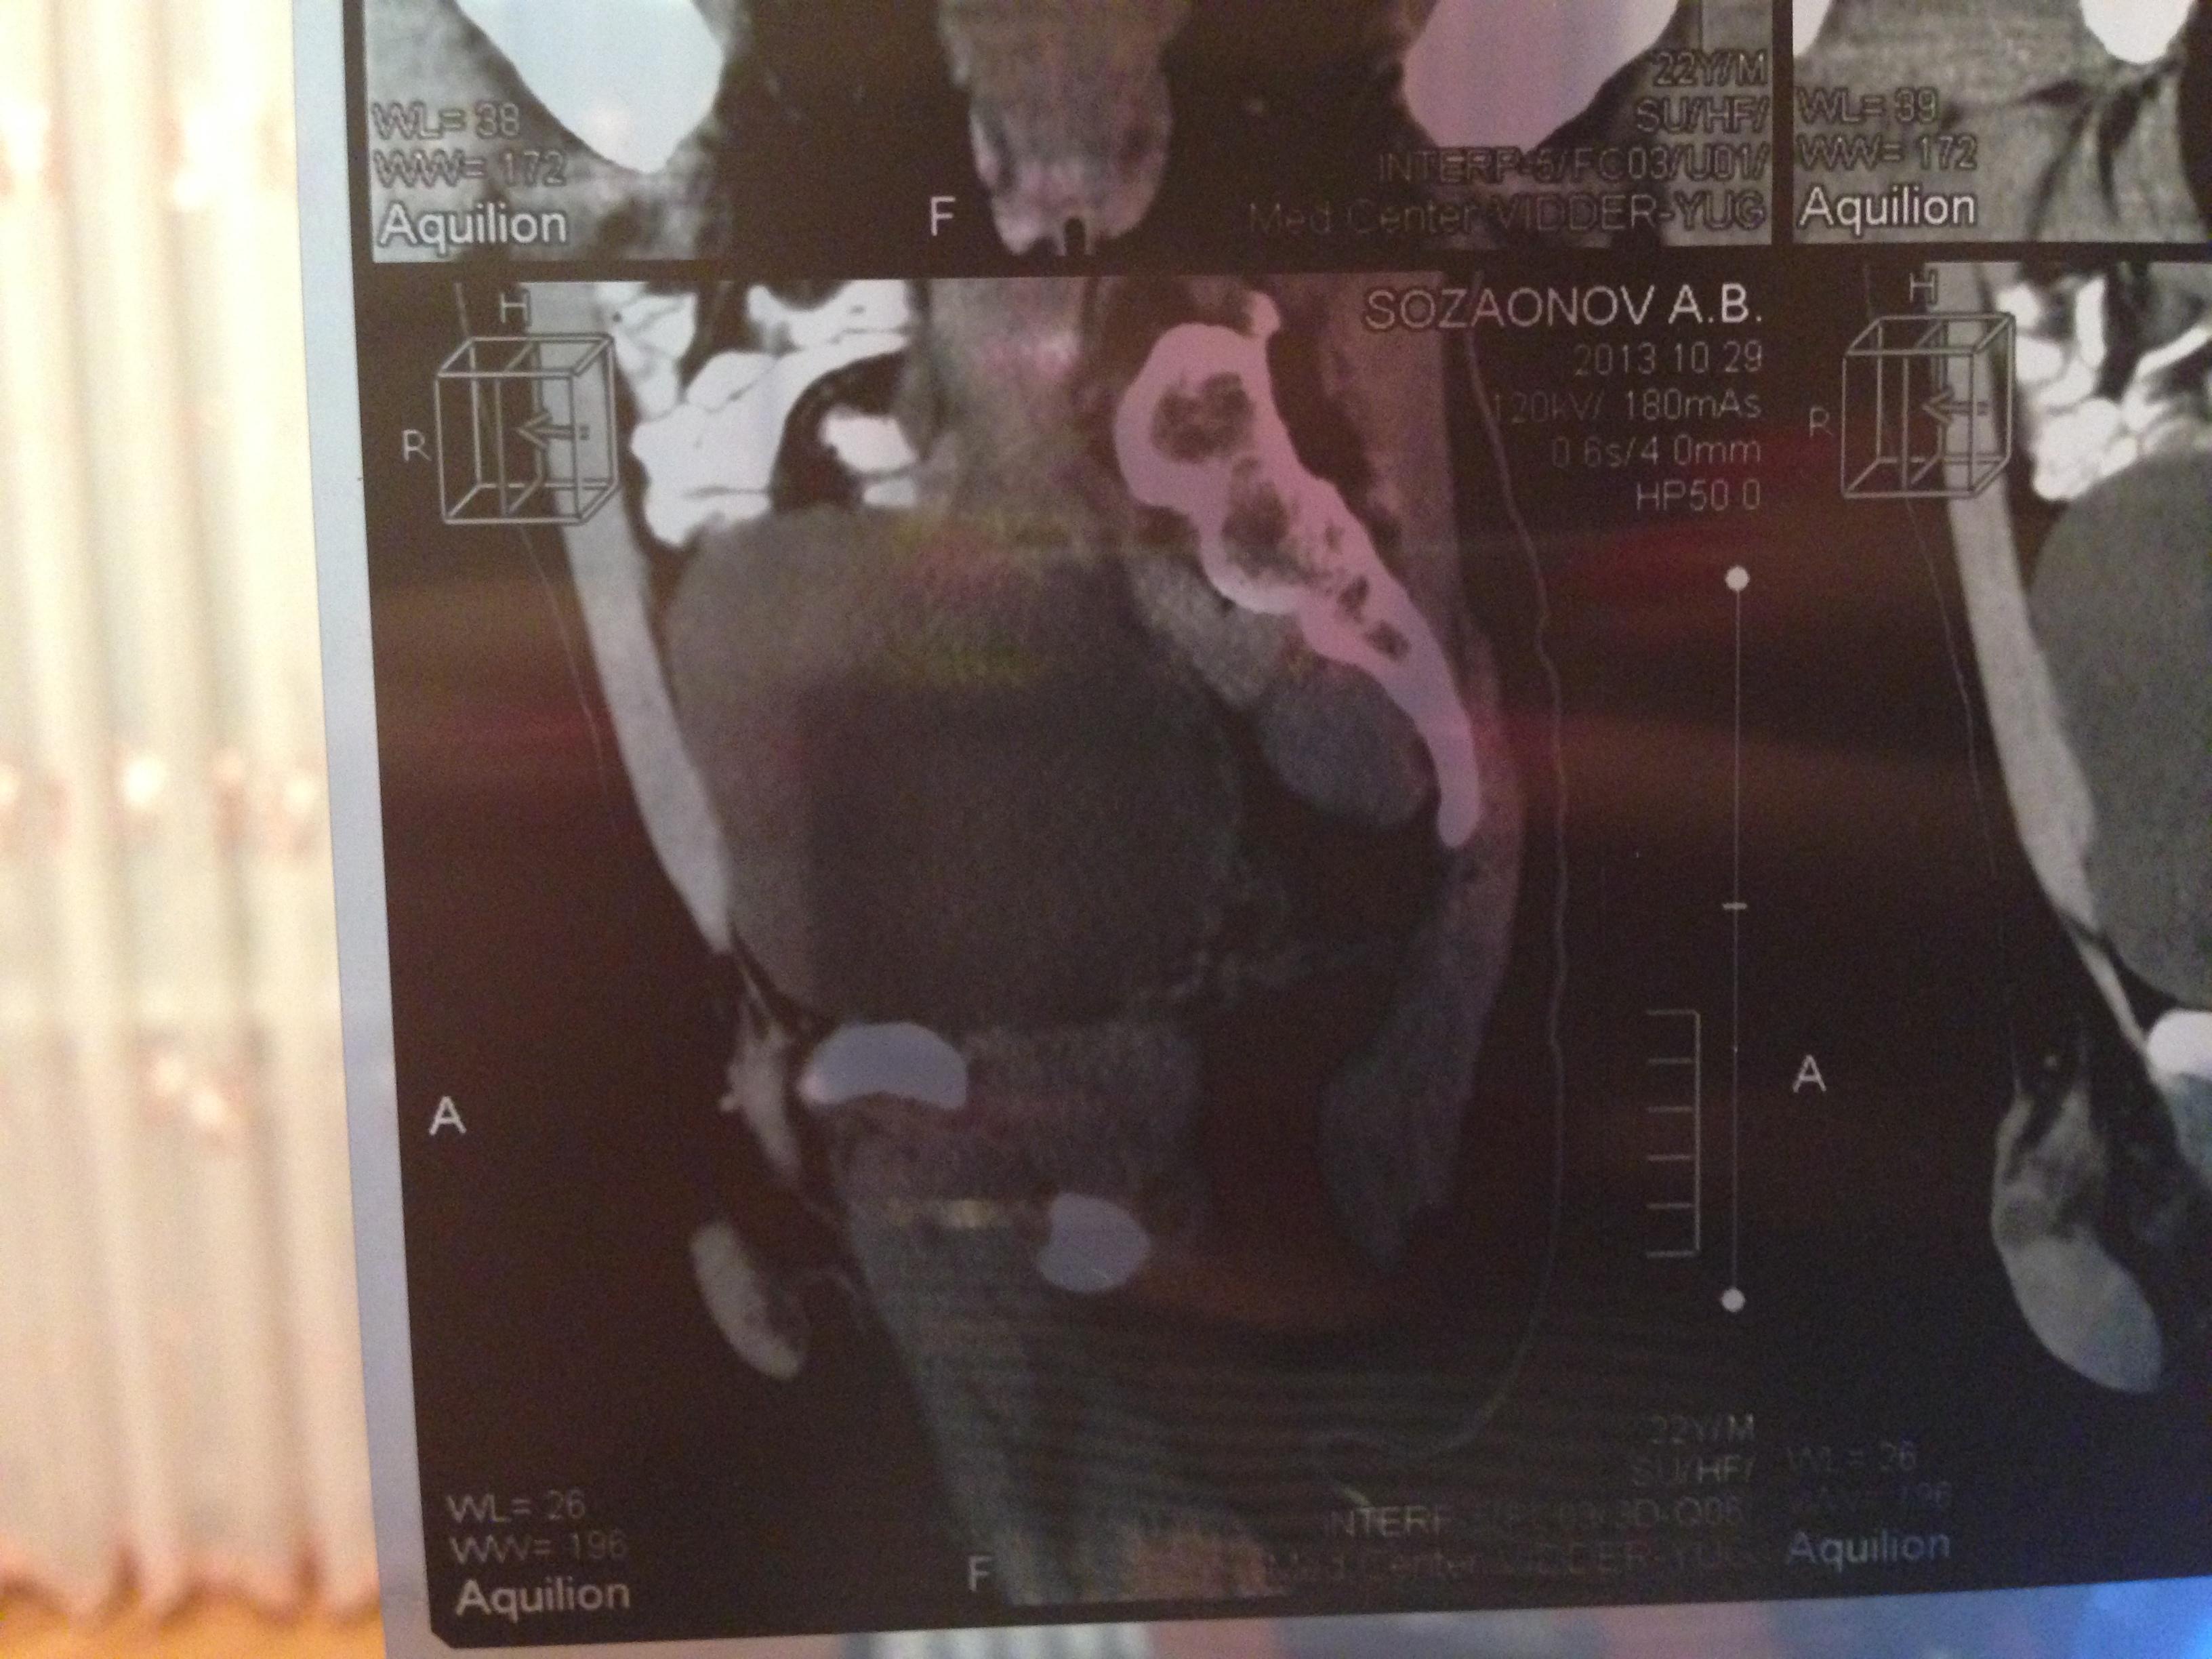

Семенные пузырьки-конфигурация не совсем типична,примерный размер правого 26*28мм.Отмечаются признаки кистовидной трансформации и микрокальцинации обоих пузырьков.Наибольшая из кист слева достигает 9 мм.Обращает на себя внимание неравномерная кальцинация стенок крупных регионарных(текстикулярных)артерий с обоих сторон.

Заключение:на момент исследования,КТ-данных за наличие внеорганных дополнительных патологических образований,лимфоденопатии или свободной жидкости в области таза не выявлено.КТ-признаки в пользу проявлений калькулезного везикулита с элементами кистовидной трансформации семенных пузырьков.